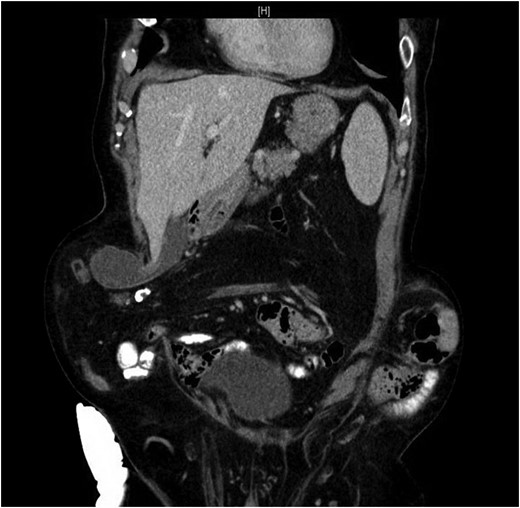

Our patient is an 89-year-old male with a history of a Hartmann’s procedure (2006) for Crohn’s disease of the sigmoid colon followed by a reversal of the colostomy with a diverting loop ileostomy (2008). Due to his comorbidities and age, the patient declined further surgery to reverse his loop ileostomy. Most recently, the patient presented to the emergency room with no ostomy output for the past 14 h, nausea and frequent burping. He reported a burning sensation around his ostomy. His physical examination revealed a large parastomal hernia in the right hemiabdomen and associated tenderness in the right upper quadrant, with no overlying skin changes. His white blood cell count was 8.1 (82.4% neutrophils), and he had normal liver function tests. A computed tomography (CT) scan of the abdomen and pelvis revealed a large parastomal hernia with a wide neck containing a distended gallbladder concerning for acute cholecystitis, as well as a small bowel obstruction with a transition point at the level of the hernia (Figs 1 and 2). A previous CT scan showed the same hernia with a nondistended gallbladder and non-obstructed bowel entering and exiting the stoma (Fig. 3).

CT from May 2017 with decompressed gallbladder and unobstructed bowel.